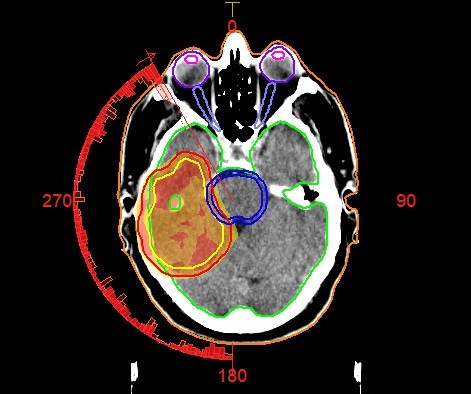

Then, specialists called medical physicists and dosimetrists work together to figure out the best way to deliver the right amount of radiation. The goal is to hit the cancer with the strongest dose while keeping the nearby healthy areas safe. This careful planning helps make your treatment both effective and safe.

The dosimetry department plays a key role in your radiotherapy treatment journey. Their main job is to make sure that the amount of radiation used during your treatment is carefully planned and precisely delivered to the cancer area, while protecting as much healthy tissue as possible. Although you may not meet the dosimetry team directly, their work is essential to the success of your treatment.

Before your radiotherapy begins, your cancer treatment team, which includes doctors, radiation therapists, and medical physicists, work together to design a treatment plan tailored specifically for you. The dosimetry team is responsible for the technical side of this process, making sure the right amount of radiation (called the “dose”) is used.

The work of the dosimetry team is essential to making sure your radiotherapy is safe, precise, and effective. Without their detailed calculations and careful planning, it would be difficult to accurately target the cancer while minimising the risk to healthy tissues. Their expertise in radiation physics and treatment planning ensures that your cancer treatment is customised specifically for you.